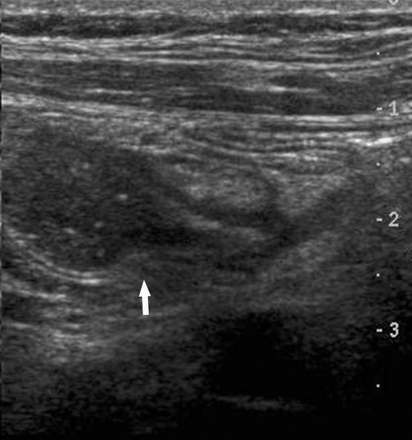

一8岁男孩出现急性右侧肋缘疼痛并呕吐。超声显示小肠梗阻。扩张和非扩张小肠肠管临界区位于右侧髂窝(图3),此区域右侧和上方的小部分的小肠肠管堆积受压成胶囊状,蠕动消失(图4)。诊断为腹内疝导致的小肠梗阻。病人而没有再做其他检查进行了手术治疗。

图3 右侧髂窝斜向扫描显示扩张和非扩张肠管的过渡区(箭头)。